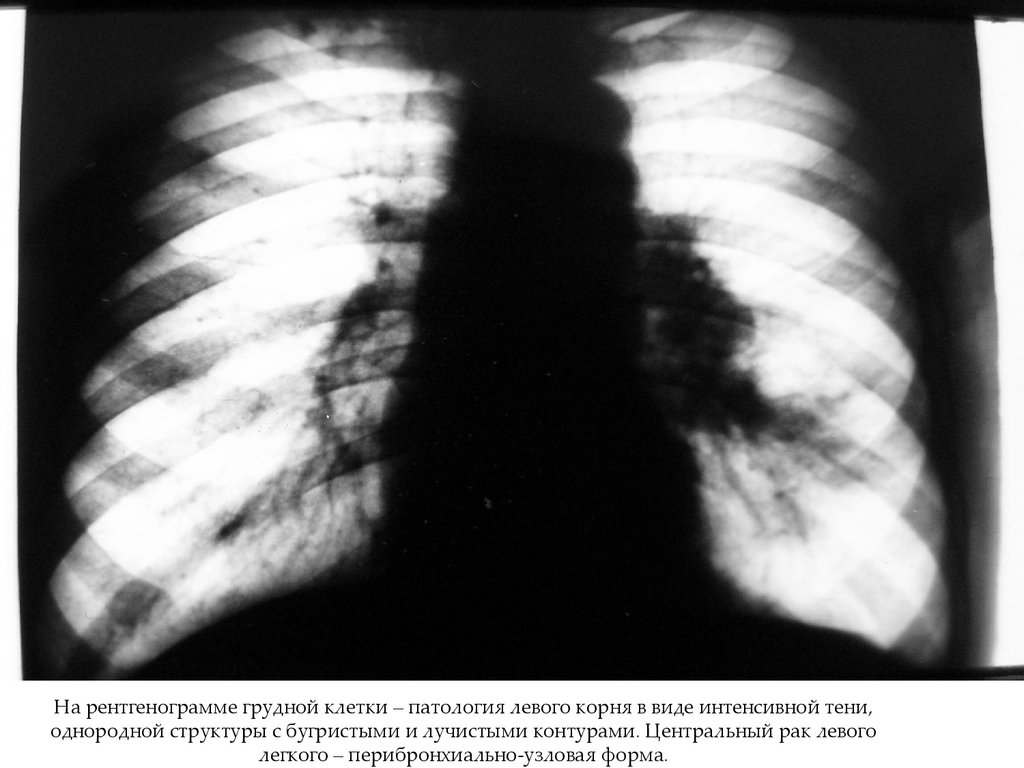

На рентгенограмме грудной клетки – патология левого корня в виде интенсивной тени,

однородной структуры с бугристыми и лучистыми контурами. Центральный рак левого

легкого – перибронхиально-узловая форма.